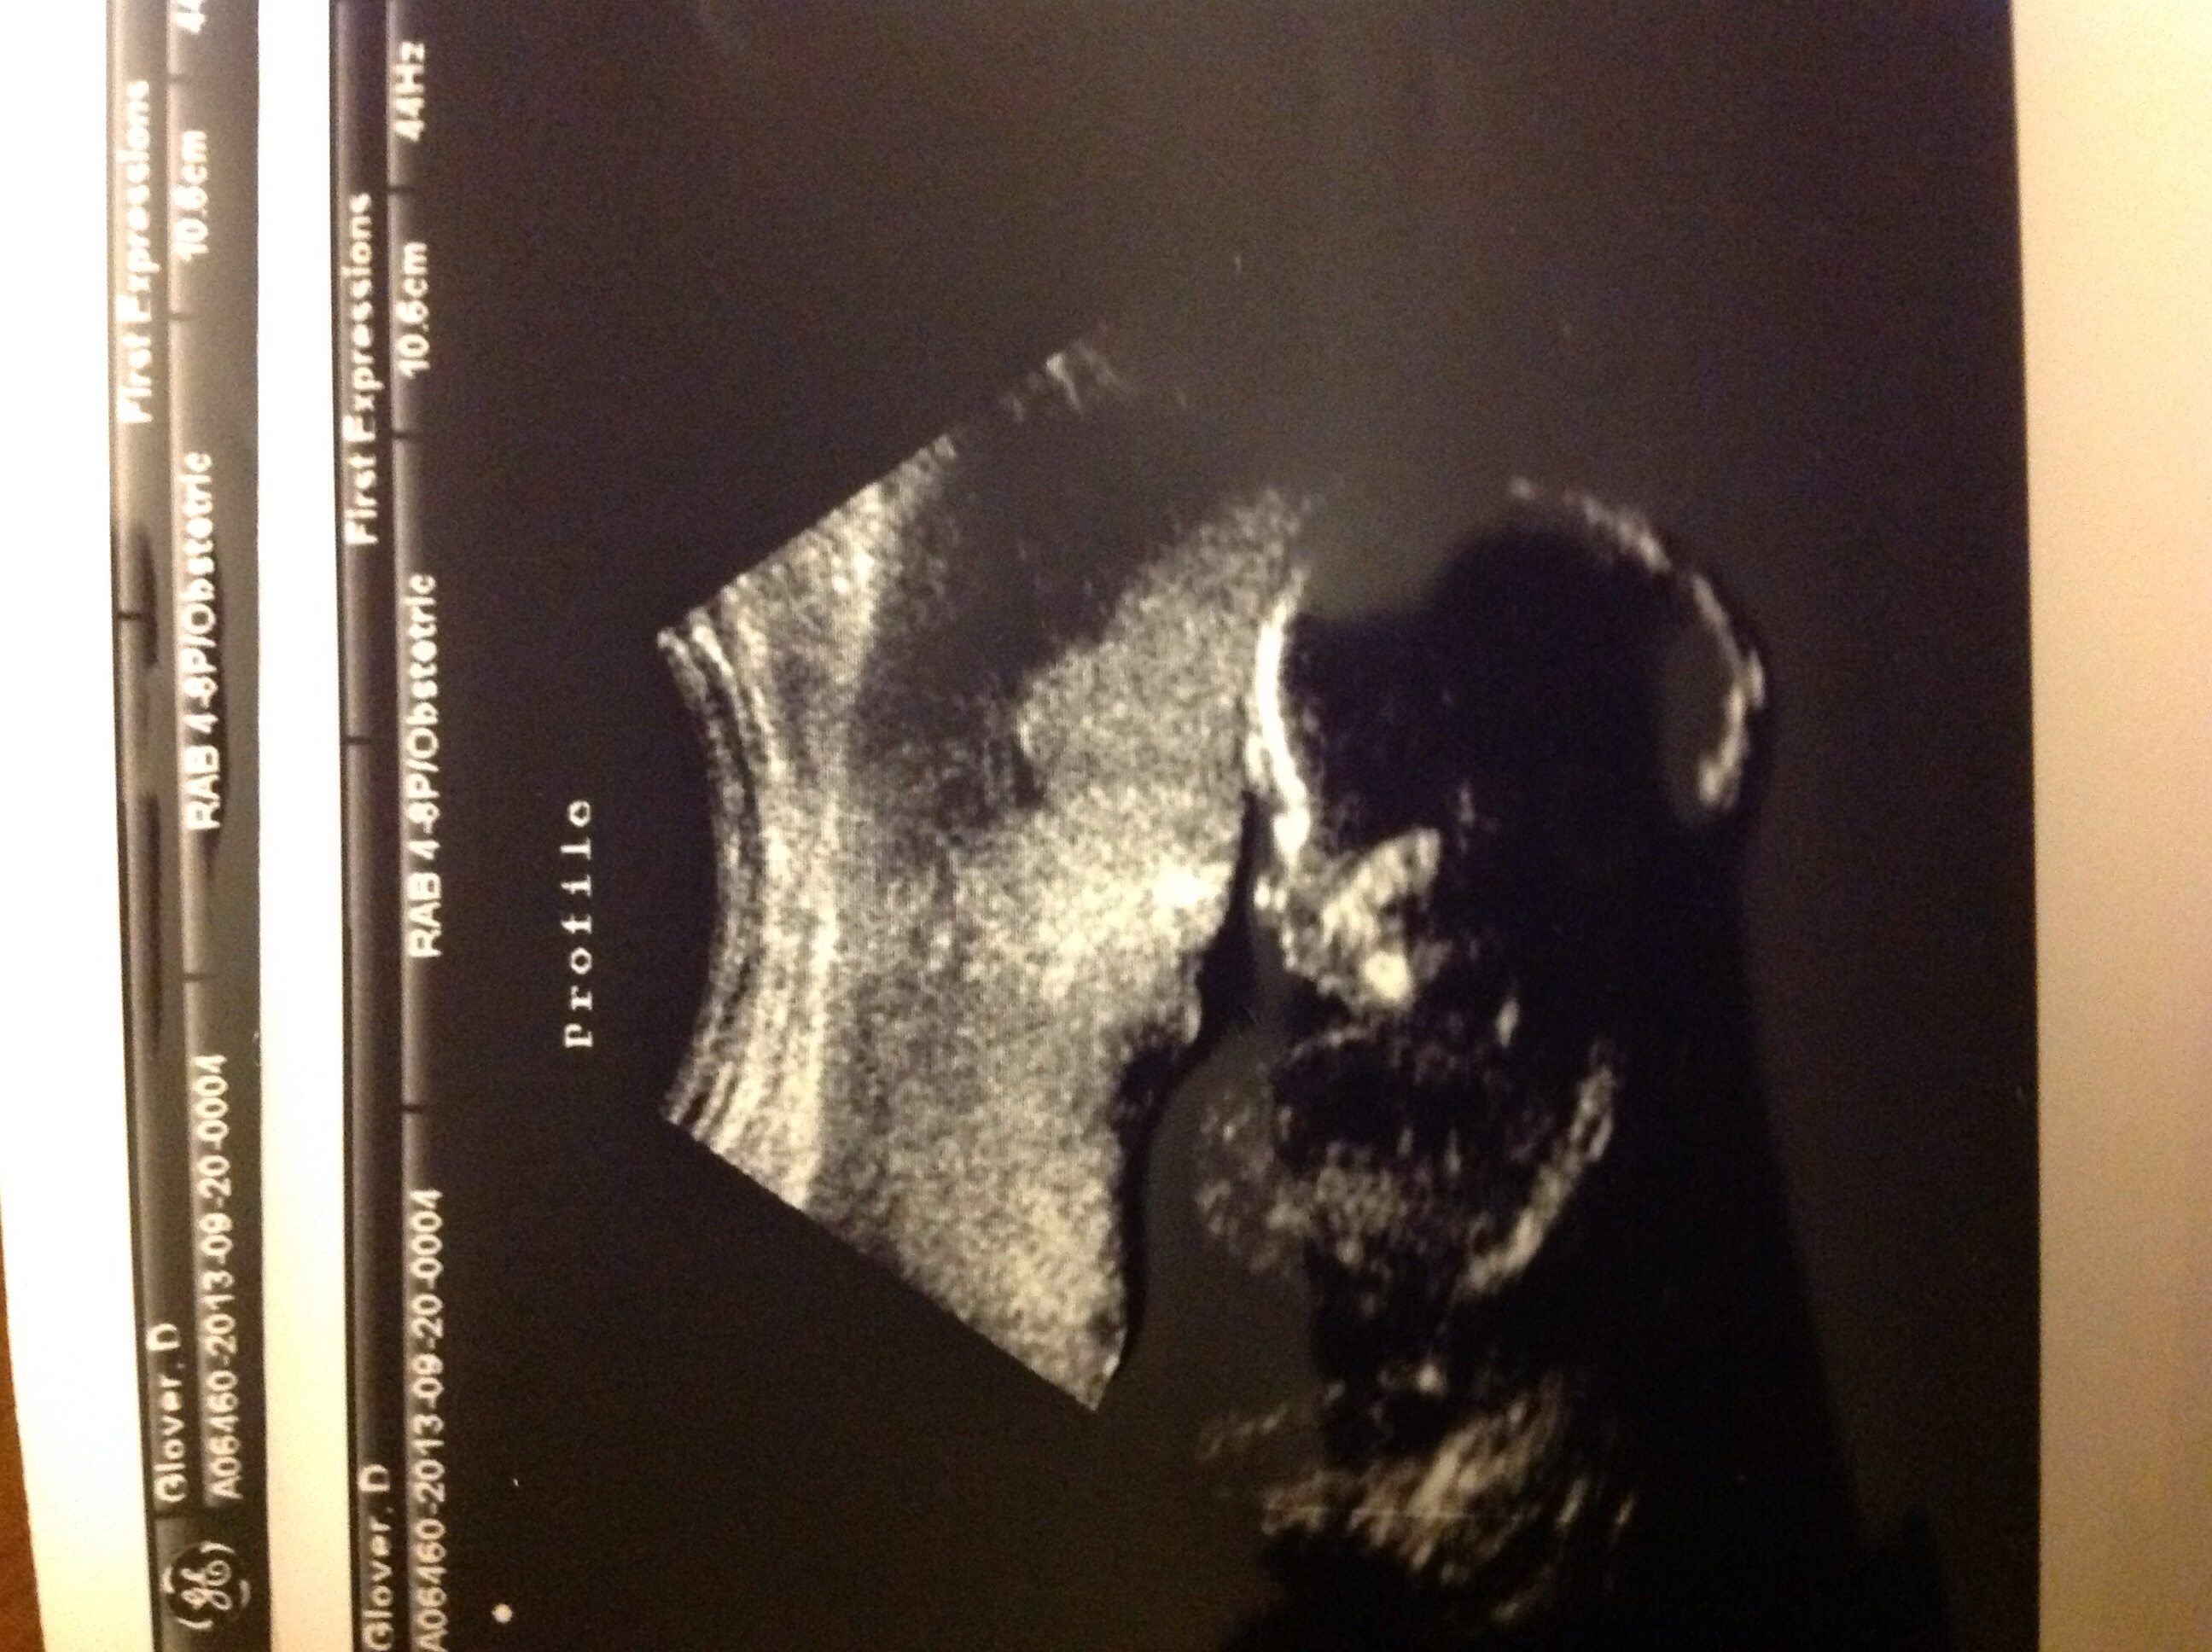

I posted this in February too sorry if you read twice, I'm right on the border!!!! On Friday I had an elective ultrasound where I found out I am having my second boy! My DH was so happy he cried, best moment of this pregnancy so far!!!! I also found out that I have an anterior placenta which makes me feel better bc I am not sure I have felt him moving yet. Then on Saturday I started spotting with sharp pains, went to the ER and they found my baby's heartbeat, checked my urine, and sent me home with instructions to follow up with primary care doctor for abdominal pain? Never even asked me for my OBs name. Needless to say I was less than happy with my experience. Well the spotting has stopped but the pain continues. My nurse came yesterday for my 17P shot and informed me to call my doctor and report my concerns to them. They have me on rest till everything stops. If it does not I have to get an ultrasound. So my question after all this is has anyone else had spotting around 16-17 weeks and if so what was the outcome? Any other ladies with 17P how is that going? It was not as bad as I thought! Hope everyone is feeling great! Happy ending is that my little boy seems to still be ok in there!!!! I will update when pain goes away or I have an ultrasound!!!!

image